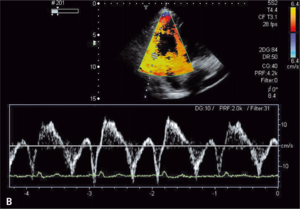

Rycina 3. Podwyższone ciśnienie skurczowe krwi w prawej komorze u chorego z toczniem rumieniowatym

układowym.

Toczeń rumieniowaty układowy